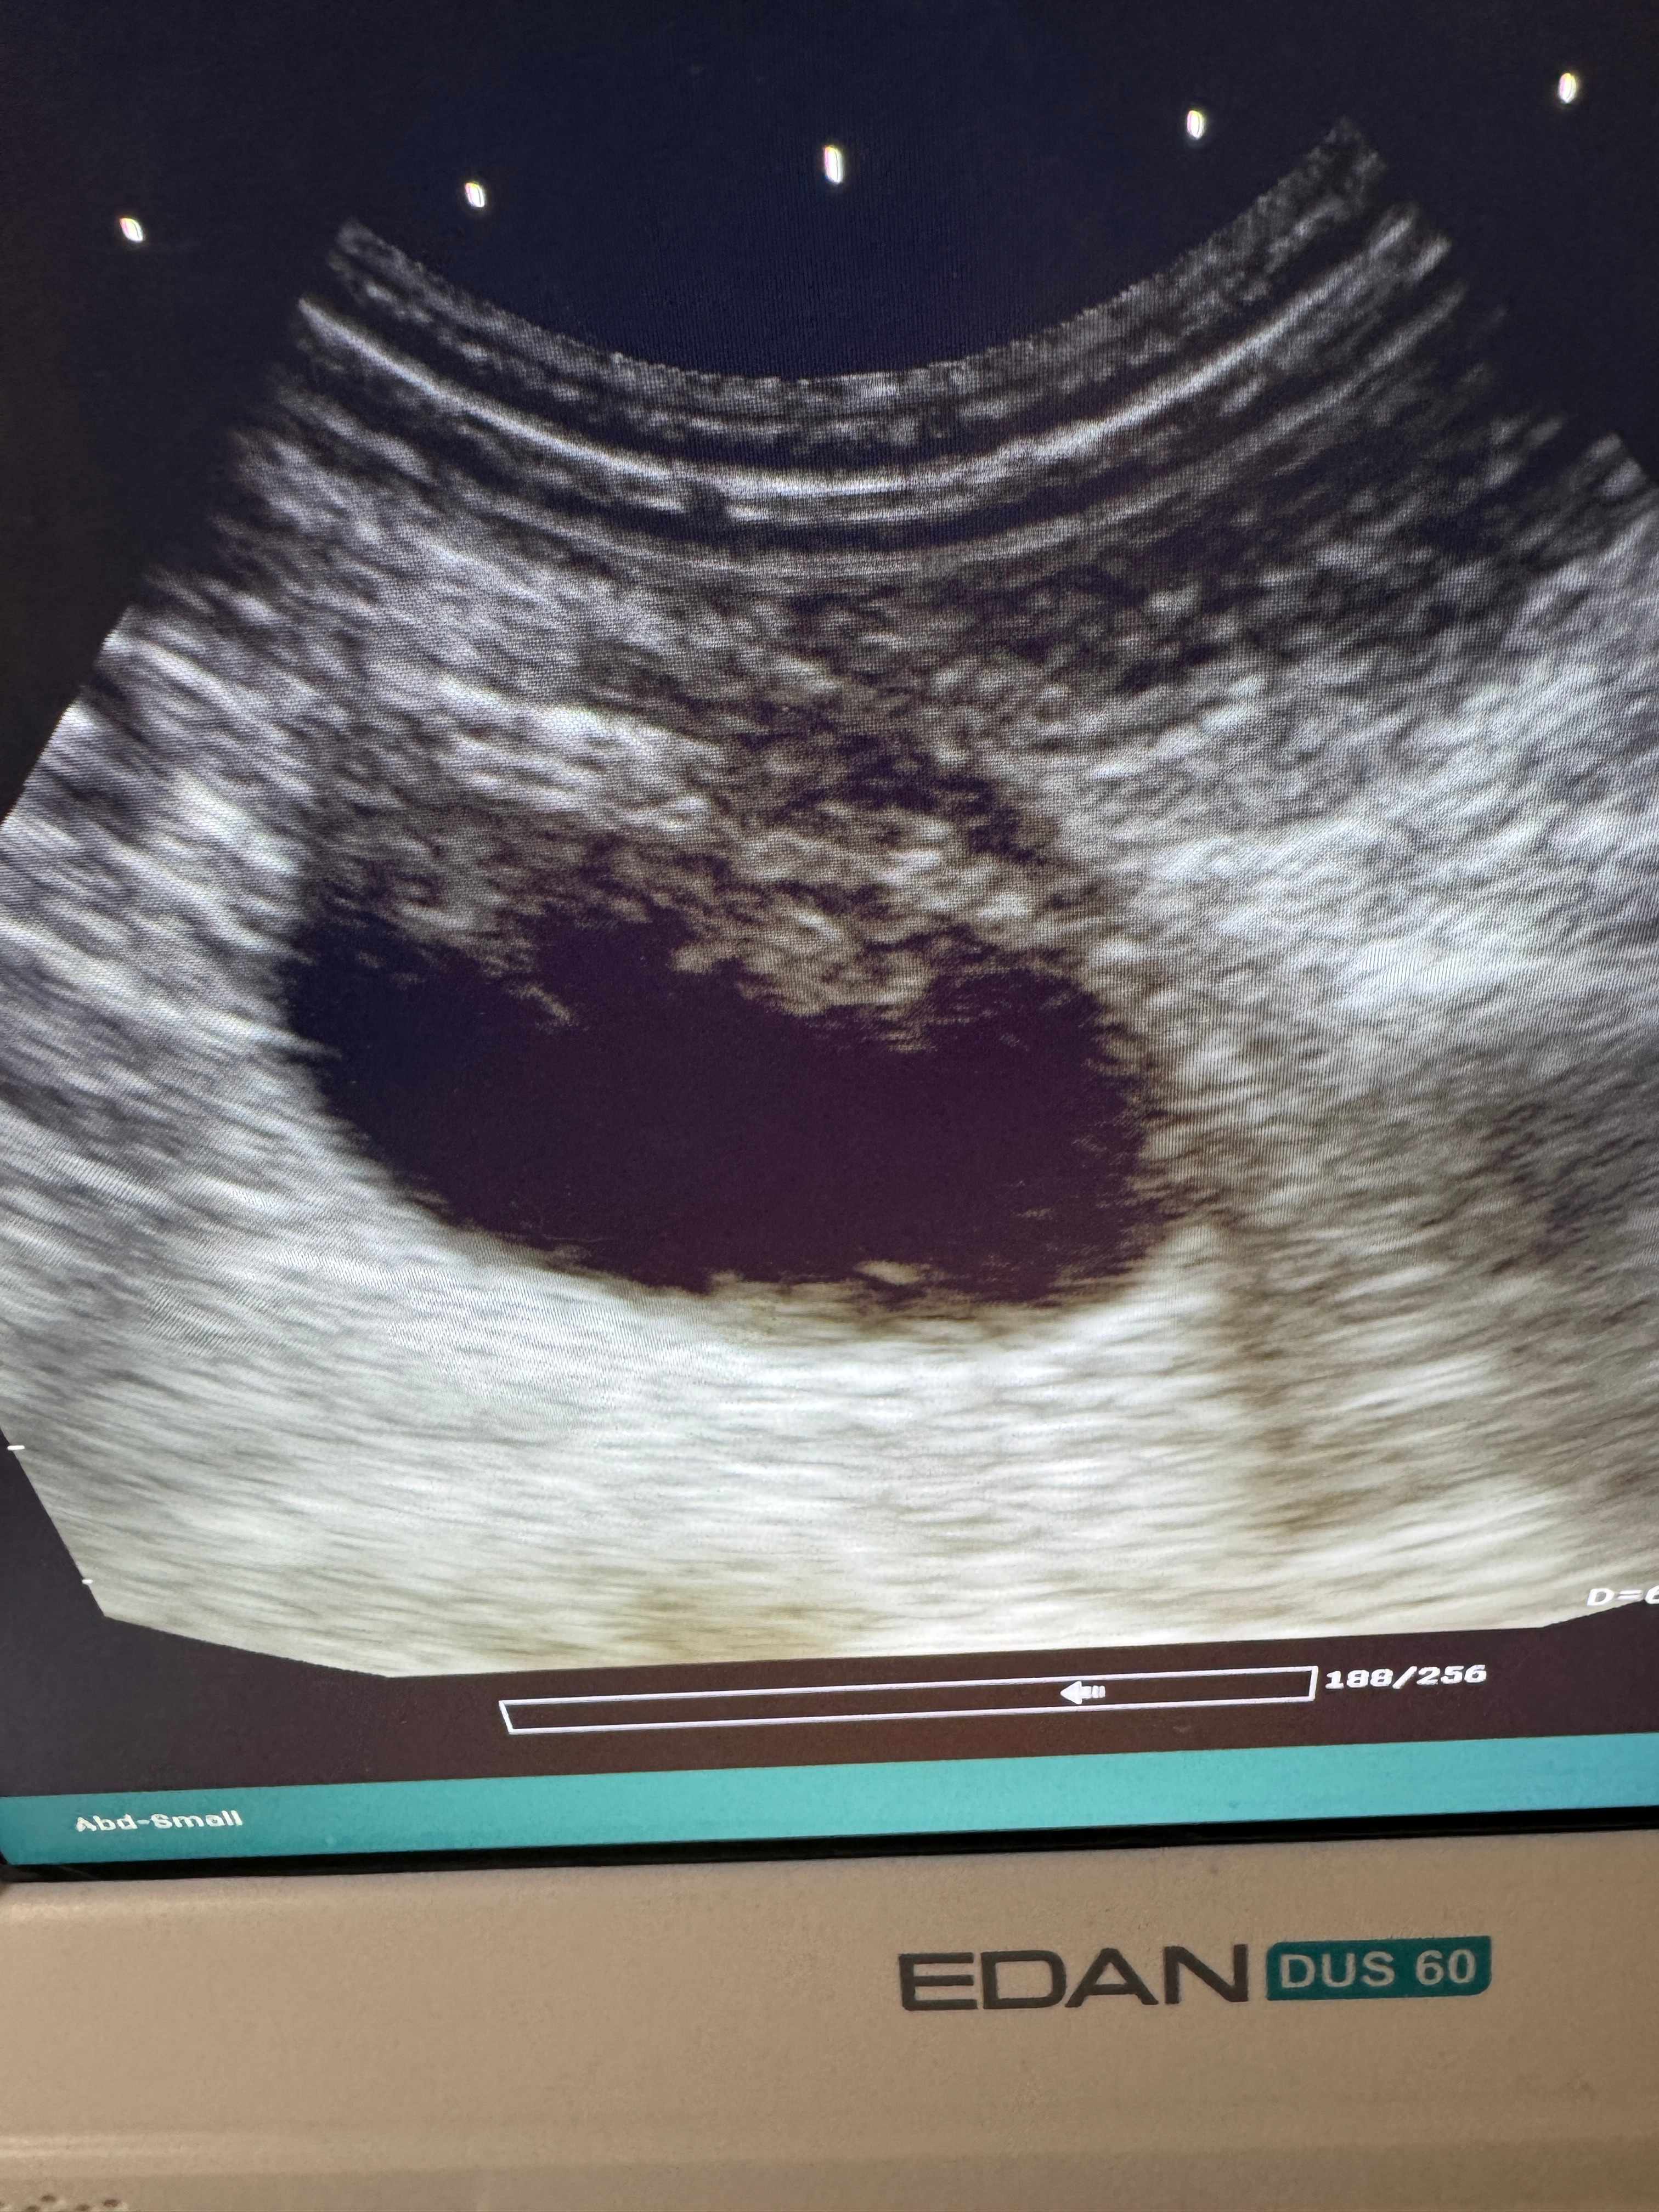

Anti-anxiety medication in early December got her largely back to normal, but around Christmastime, her symptoms showed up again - visible discomfort when walking or laying on her stomach, peeing multiple times an hour, sometimes where she wasn’t supposed to, and lots of blood in the pee. Once again, there were no bacteria present, so more imaging was ordered. On New Years Eve, a scan confirmed a fairly large mass in her bladder that our vet had been monitoring as a possibility for a few weeks, though the extra junk in the bladder from the UTIs made it difficult, if not impossible, to see.

This mass is now thought to be a transitional-cell carcinoma, though the biopsy was inconclusive. After meeting with an oncologist on Monday, January 12, we’ve determined that the best course of action is to surgically remove the mass, regardless of what it is. Sassy is otherwise perfectly healthy for her age and all her other blood work and vital signs are about as good as can be expected for a senior cat. As long as the mass comes out soon, the prognosis is very good. Both the oncologist and our regular vet believe that the cancer has not spread yet and that it’s likely in a fairly easy-to-operate-on part of the bladder. If we do not get the surgery, she’s got maybe 3-4 increasingly uncomfortable months left. If we do, she’s got “probably another year, at least" during which her quality of life will still be about as good as she could ask for.